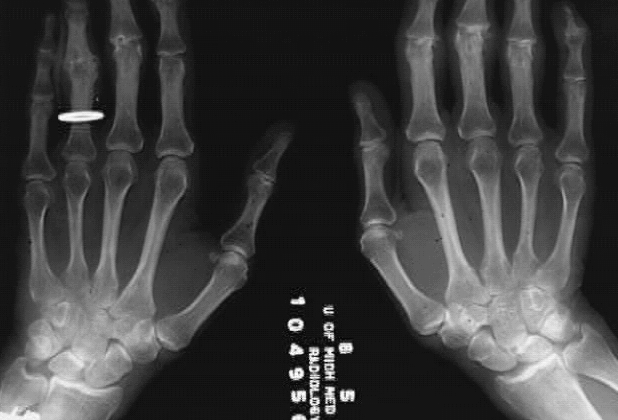

Upper Limbs:Wrist Bones Two hands: